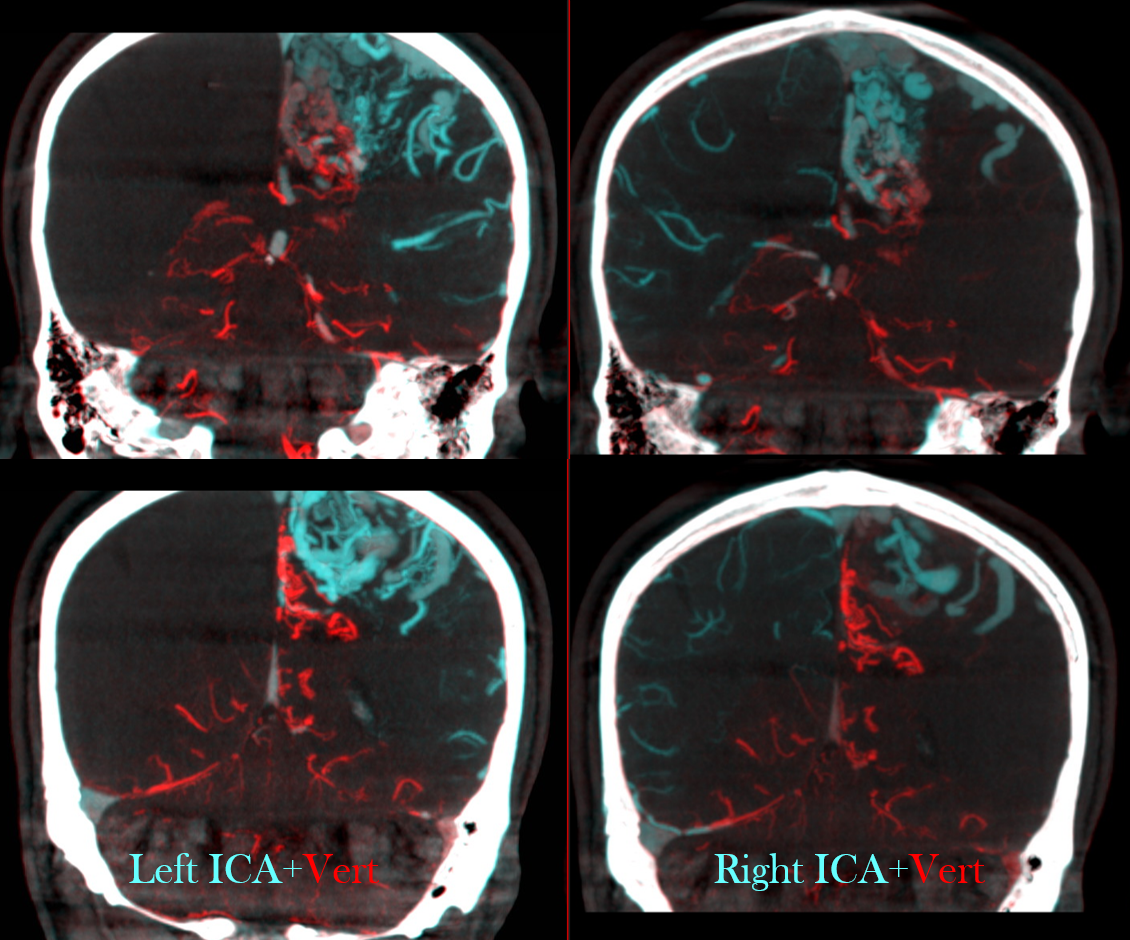

Another suer useful tool is the fusion of two different datasets (one for each AVM feeder).

First of all, open one of the two (or three, or more) datasets; then activate the fusion option and the select the dataset you want to fuse.

Then coregister the datasets; if the results are not optimal, you can manually improve the correspondence of the two datasets.

These are examples of a complex AVM. Unfortunately, we cannot save the fused datasets as a new dataset to be imported in the GammaPlan software, but just as videos.

Here we see fusion of right (blue) and left (red) ICAs in the upper line and right ICA (red) and posterior circulation (blue) in the lower line. In white you see the cast of glue injected into some large AV shunts before GK.

Although this page is not about embo technique, or outcome, or whatever multiple clinical itch questions or comments you might have, the point to be made is that gamma knife does a terrible job with macro / large intranidal shunts. If there is any chance for it to work at all, close the big shunts sub selectively and maybe some of the vein (just not the whole vein…) and gamma knife the smaller vessels which are probably not even part of the nidus to begin with… It does work better.

Note that a cyanoacrylate was used here, not EvOH. That’s why anyone who wants to attack an AVM should know how to use glue. This job is for glue.